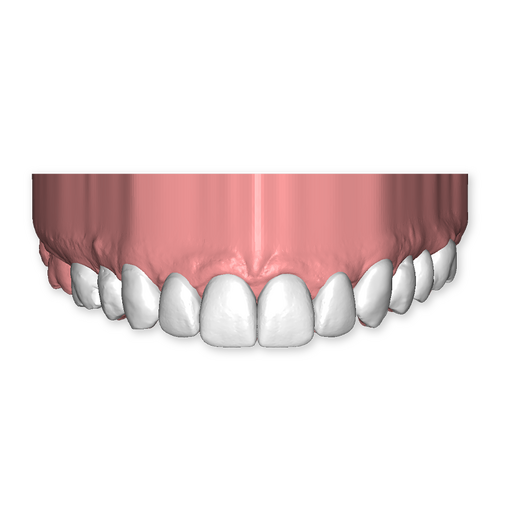

The DSD Interdisciplinary is a digital wax up of the upper and lower arches, designed considering a facially-driven, clinical and functional analysis of the patient.

It is our most comprehensive planning option, and includes all the 3D treatment simulations needed for each case, such as ortho, perio, implants, grafts and orthognathic surgery.